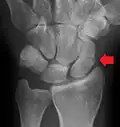

Fracture of the tubercle of the scaphoid bone of the wrist